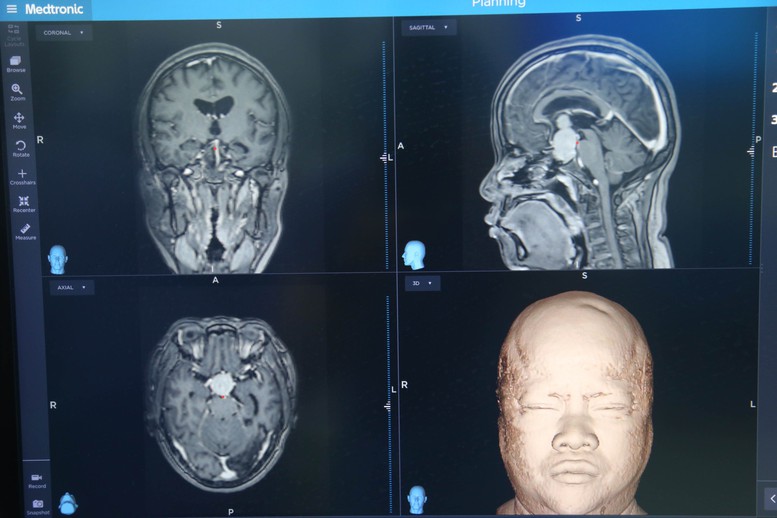

Mới đây, các bác sĩ của Bệnh viện Hữu nghị Việt Đức triển khai phương pháp kết hợp mổ phối hợp nội soi đường mũi và đường mở sọ qua vi phẫu cho một bệnh nhân nữ, 55 tuổi, ở Hà Nội. Trước đó, bệnh nhân bị mắt kém, chân đau trong thời gian dài.

Khi đi khám, người bệnh phát hiện mắc u tế bào tuyến yên khổng lồ, mắt trái không nhìn thấy, không có phản xạ với ánh sáng, mắt phải nhìn được 3/10. Bệnh nhân đã 2 lần mổ vào năm 2021 và 2023, mặc dù mắt có nhìn rõ hơn một chút nhưng bệnh tái phát nhiều lần.

Cách đây 2 tuần, người bệnh được chỉ định phẫu thuật kết hợp 2 kỹ thuật mổ phối hợp nội soi đường mũi và đường mở sọ qua vi phẫu tại Bệnh viện Hữu nghị Việt Đức.

Trao đổi với phóng viên, TS.BS Nguyễn Duy Tuyển, Trưởng khoa Phẫu thuật thần kinh 2, Bệnh viện Hữu nghị Việt Đức cho biết, trước đây, bệnh nhân này được phẫu thuật 2 lần với 2 kỹ thuật đơn lẻ, tức là hoặc nội soi hoặc mổ mở sọ. Tuy nhiên, với các trường hợp bị u tế bào tuyến yên khổng lồ, khi áp dụng 1 trong 2 kỹ thuật đơn lẻ này, người bệnh thường bị tái phát và phải phẫu thuật lại.

“Bệnh nhân này chỉ là 1 trong số không ít bệnh nhân mắc u tuyến yên khổng lồ bị tái phát nhiều lần. Vì vậy, chúng tôi luôn trăn trở làm thế nào để hạn chế mức thấp nhất người bệnh bị tái phát. Đến tháng 4/2025, lần đầu tiên chúng tôi đã triển khai thành công kết hợp 2 kỹ thuật này cùng lúc để điều trị cho người bệnh cũng mắc u tế bào tuyến yên khổng lồ, khiến thị giác bị suy giảm trầm trọng”, Ths Nguyễn Duy Tuyển chia sẻ.